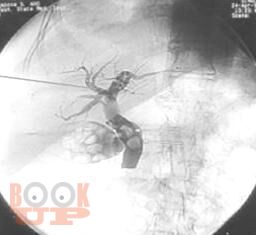

Неотложная хирургия - одно из наиболее актуальных, сложных и ответственных направлений хирургии. Пациенты пожилого и старческого возраста с механической желтухой различной этиологии толстой кишки составляют значительный контингент, госпитализируемый в хирургические стационары по экстренным показаниям. Издание реализовано с учетом опыта сотрудников кафедры и современных представлений о патогенезе, методах эндоскопической диагностики, клинических проявлениях и основных принципах лечения больных синдромом механической желтухи, обусловленной осложнениями патологии гепатопанкреатодуоденальной зоны и желудочно-кишечного тракта. Успех в лечении таких пациентов во многом зависит от своевременности и точности постановки диагноза.